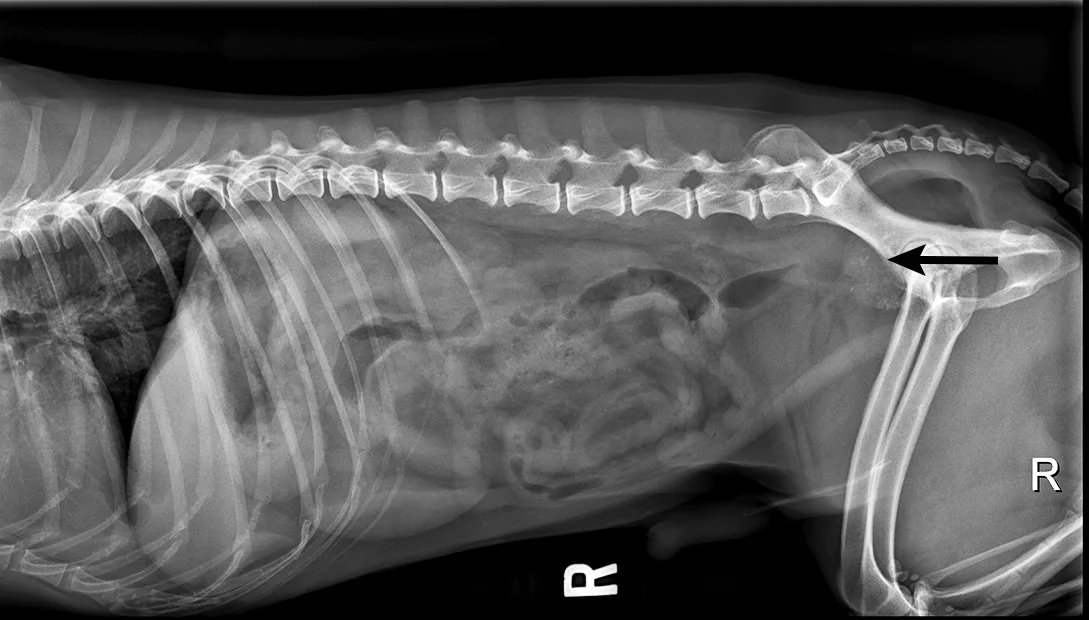

Lateral abdominal radiograph of a dog.

FIGURE 3

Radiograph of an enlarged and mineralized prostate (arrow) in a dog diagnosed with prostatic carcinoma based on DNA urine testing. Image courtesy of Merrilee Holland, DVM, DACVR

Other organs (eg, prostate in males) may be palpable depending on patient size. Intact males commonly have benign prostatic hypertrophy or bacterial prostatitis. Additional testing (eg, radiography, ultrasonography, urinalysis, urine culture) may be needed. As with transitional cell carcinoma, molecular tests can be submitted for diagnosis of prostatic carcinoma. DNA-based diagnostics are highly sensitive and specific, making these tests noninvasive and useful for diagnosis of transitional and prostatic carcinoma (Figure 3).12,13